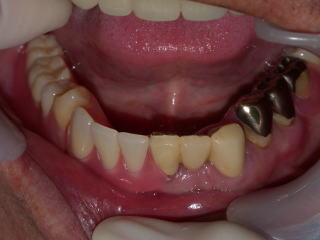

下の前歯は数年前に抜けて旧義歯に増歯したままです。

下の義歯はバネのないクラスプレス義歯です。